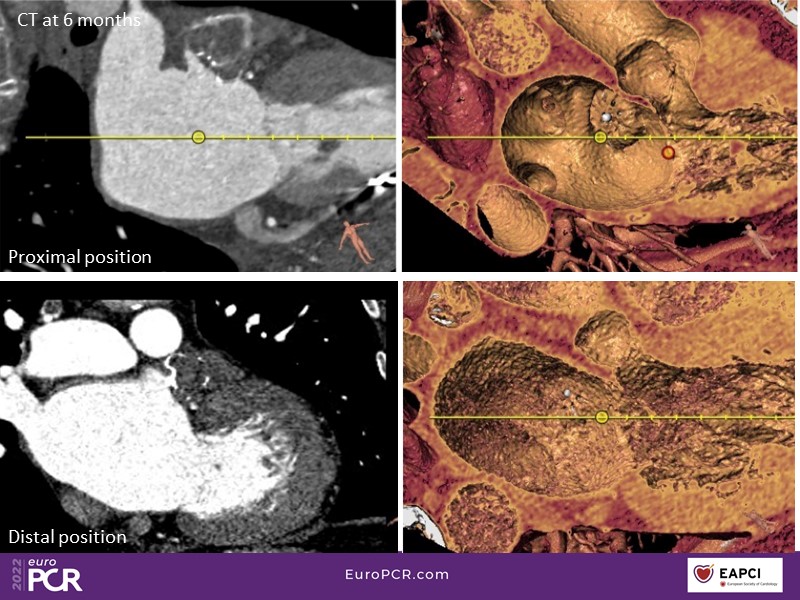

Based on a pre-registered case study of a 68-year-old male patient, DG, who presented with atrial fibrillation, intracranial bleeding on warfarin, and compartment syndrome secondary to bleeding from warfarin, this EuroPCR 2022 session will allow you to discuss the challenges of treating AF patients with previous intracranial bleed, understand the role and functioning of a heart-brain team, and showcase the safety of Watchman FLX in specific subsets of patients.